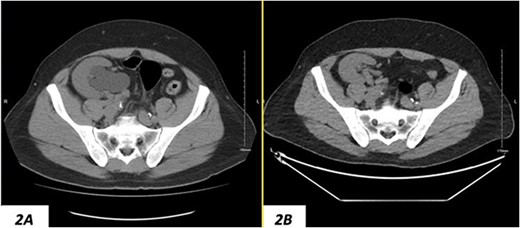

(A) Hydronephrosis of the allograft ureter on preoperative cross-sectional CT scan; (B) significant improvement of hydronephrosis on the 10-month postoperative image.